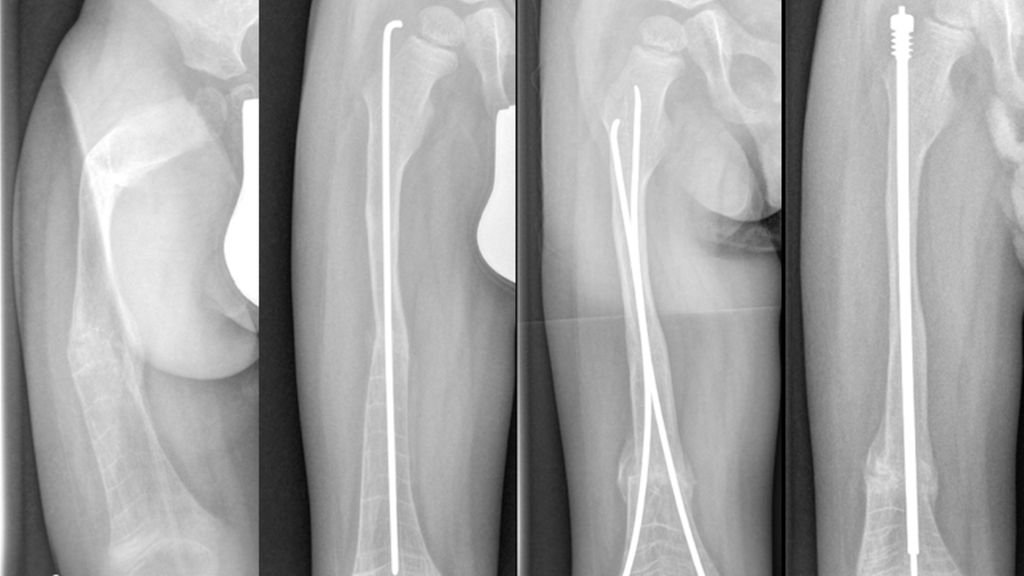

Während bei Kleinkindern aufgrund des geringen intramedullären Durchmessers häufig nur ein Bohrdraht zur Schienung eingebracht wird, können bei größeren Kindern mitwachsende intramedulläre Nägel verwendet werden (Teleskopnagel, wie zum Beispiel Fassier-Duval-Nagel, Abb. 1). Diese ermöglichen eine langstreckige Stabilisierung von der proximalen zur distalen Tibiaepiphyse sowie vom Trochanter major bis zur distalen Femurepiphyse. Das Einbringen intramedullärer Implantate kann durch ausgeprägte Deformitäten, kurze Extremitäten und iatrogene Frakturen kompliziert werden. Plattenosteosynthesen sind aufgrund des hohen Risikos für an die Platte angrenzende Frakturen als Alleinversorgung zu vermeiden.

Abb. 1: A) 2 Jahre alter Knabe, OI 3 mit hoher Frakturrate und Procurvatum/Varus/Maltorsionsdeformität Femur rechts, B) Erstkorrektur mit Bohrdraht nach Doppelosteotomie, C) Akutfraktur unfallchirurgisch extern mit retrograden ESINS versorgt, D) geplanter Umstieg von ESINS auf Fassier-Duval-Teleskopnagel mit erneuter Osteotomie im Alter von 4 Jahren